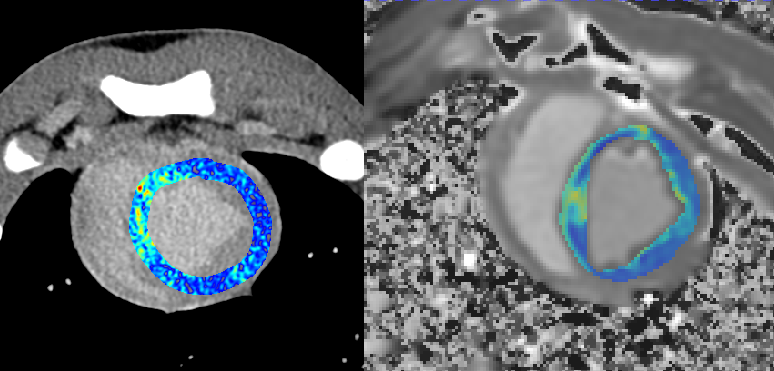

uCT SiriuX落地临床验证中,我们切身体会了这款设备的全脏器覆盖能谱成像功能,可在单心动周期内完成全心能谱采集,提供多种能谱图像类型。

例如,虚拟单能图像可优化冠脉图像对比度,有效消除血管管腔中钙化导致的晕状伪影,确保准确的血管评估;同时,基于能谱图像的物质识别技术,还可进行斑块成分分析,进一步提升诊断精度。

什么是联影ct真香预警?联影医疗双宽体双源CT大揭秘!TA竟然可以看到心脏的高清运动!_https://www.jmylbn.com_新闻资讯_第22张

什么是联影ct真香预警?联影医疗双宽体双源CT大揭秘!TA竟然可以看到心脏的高清运动!_https://www.jmylbn.com_新闻资讯_第23张

全新双宽体CT系统uCT SiriuX凭借全脏器覆盖能力,实现 “全域” 心脏多维成像评估,即注射一次对比剂可同时获取冠脉CTA、心肌灌注、心脏能谱成像和心肌延迟强化等多维图像信息,初步验证结果与DSA、MR心肌灌注、MR延迟强化等金标准影像手段有较高一致性。这对于需要同时进行解剖与功能性评估的患者来说,方便省事了许多。

CT心肌灌注 VS MR心肌灌注

CT心肌延迟显像 VS MR ECV(心肌细胞外容积)

此外,通过心脏能谱成像的虚拟高能图像,系统能够有效抑制严重钙化和支架场景下的伪影。在心肌灌注成像的基础上,结合能谱成像的碘定量分析,有望解决CT值差异带来的灌注参数标准化难题,进一步提高诊断精度。

什么是联影ct真香预警?联影医疗双宽体双源CT大揭秘!TA竟然可以看到心脏的高清运动!_https://www.jmylbn.com_新闻资讯_第27张

CT心脏能谱 VS MR PSIR(相位敏感反转恢复)